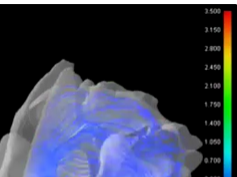

Visualization of the Supraglottis During Suprglottoplasty for Laryngomalacia Using 3D Endoscopy